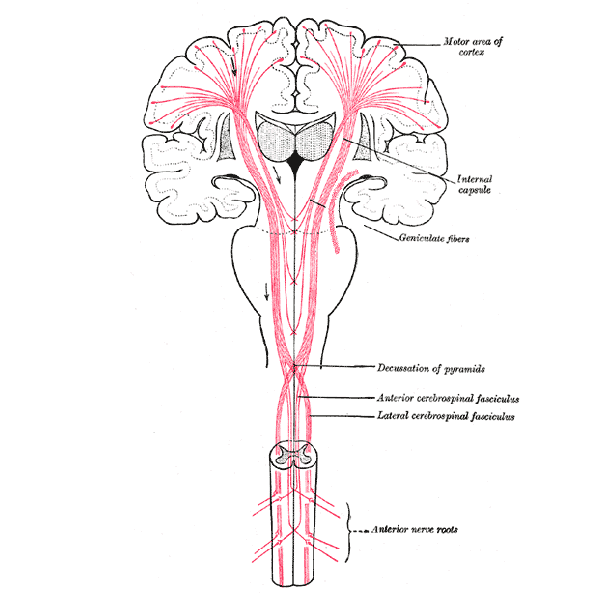

De functies van de neocortex zijn verdeeld over de vele windingen, van basaal aan de achterkant naar het meest abstract denkend aan de voorkant.

De functies van de neocortex zijn verdeeld over de vele windingen, van basaal aan de achterkant naar het meest abstract denkend aan de voorkant.

De functies van de neocortex zijn verdeeld over de vele windingen, van basaal aan de achterkant naar het meest abstract denkend aan de voorkant.

De functies van de neocortex zijn verdeeld over de vele windingen, van basaal aan de achterkant naar het meest abstract denkend aan de voorkant.

De functies van de neocortex zijn verdeeld over de vele windingen, van basaal aan de achterkant naar het meest abstract denkend aan de voorkant.